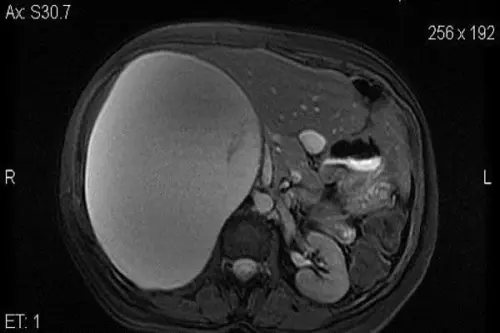

Un tumore di dimensioni enormi è stato asportato dal corpo di una donna attraverso un intervento record. È successo a La Maddalena dove con un’operazione durata tre ore e mezza è stato asportata una massa tumorale da 20 centimetri.

Un intervento record è stato eseguito da una equipe composta da Pietro Mezzatesta, Lucio Mandalà, Luigi Casà e Antonio Noto dell’Unità operativa complessa di Chirurgia de La Maddalena. Ad essere sottoposta a questa operazione una donna di 39 anni, colpita da un tumore al surrene. Nonostante la presenza della massa tumorale la donna aveva da poco partorito grazie ad un intervento chirurgico mini invasivo.Massa tumorale crescente

La donna, che aveva scoperto della neoplasia durante la gestazione. Questa le era stata ridotta in un’altra struttura palermitana per favorire il parto. Si era sperato, pertanto di una definitiva risoluzione del problema. Qualche settimana dopo il parto, però, la massa tumorale ha ripreso a crescere. Le dimensioni sono diventate enormi ed è stata notata una vistosa compressione degli organi interni, causando alla paziente disturbi via via più gravi. La donna si è pertanto rivolta alla struttura "La Maddalena", dove è stata sottoposta ad accertamenti atti a indagare sull'origine della massa da cui è seguito l’intervento chirurgico eseguito in laparoscopia. L’intervento è stato reso necessario dalla notevole compressione della massa tumorale su organi vitali come il fegato ed il rene.Intervento durato 3 ore e mezza

La scelta della laparoscopia è stata fatta per evitare alla neo mamma un’incisione di notevoli dimensioni, che avrebbe causato alla donna effetti devastanti. L’intervento, molto complesso è durato 3 ore e mezza. I medici durante l’operazione hanno scoperto che era il surrene, l’organo da cui traeva origine la massa tumorale di 20 centimetri. Lo stesso surrene, di dimensioni paragonabili ad una castagna, non era più riconoscibile. L’operazione è stata effettuata nel novembre del 2017. Prima della quale è stata necessaria una riduzione della parte liquida del tumore, per poi poter intervenire in laparoscopia sullo stesso. Per eseguire un’operazione, infatti, con questa tecnica è richiesta immissione di un gas inerte per creare spazi tra gli organi nella cavità addominale. La paziente , che ora si è sottoposta a controllo di routine, appare in buone condizioni di salute.Articolo Precedente